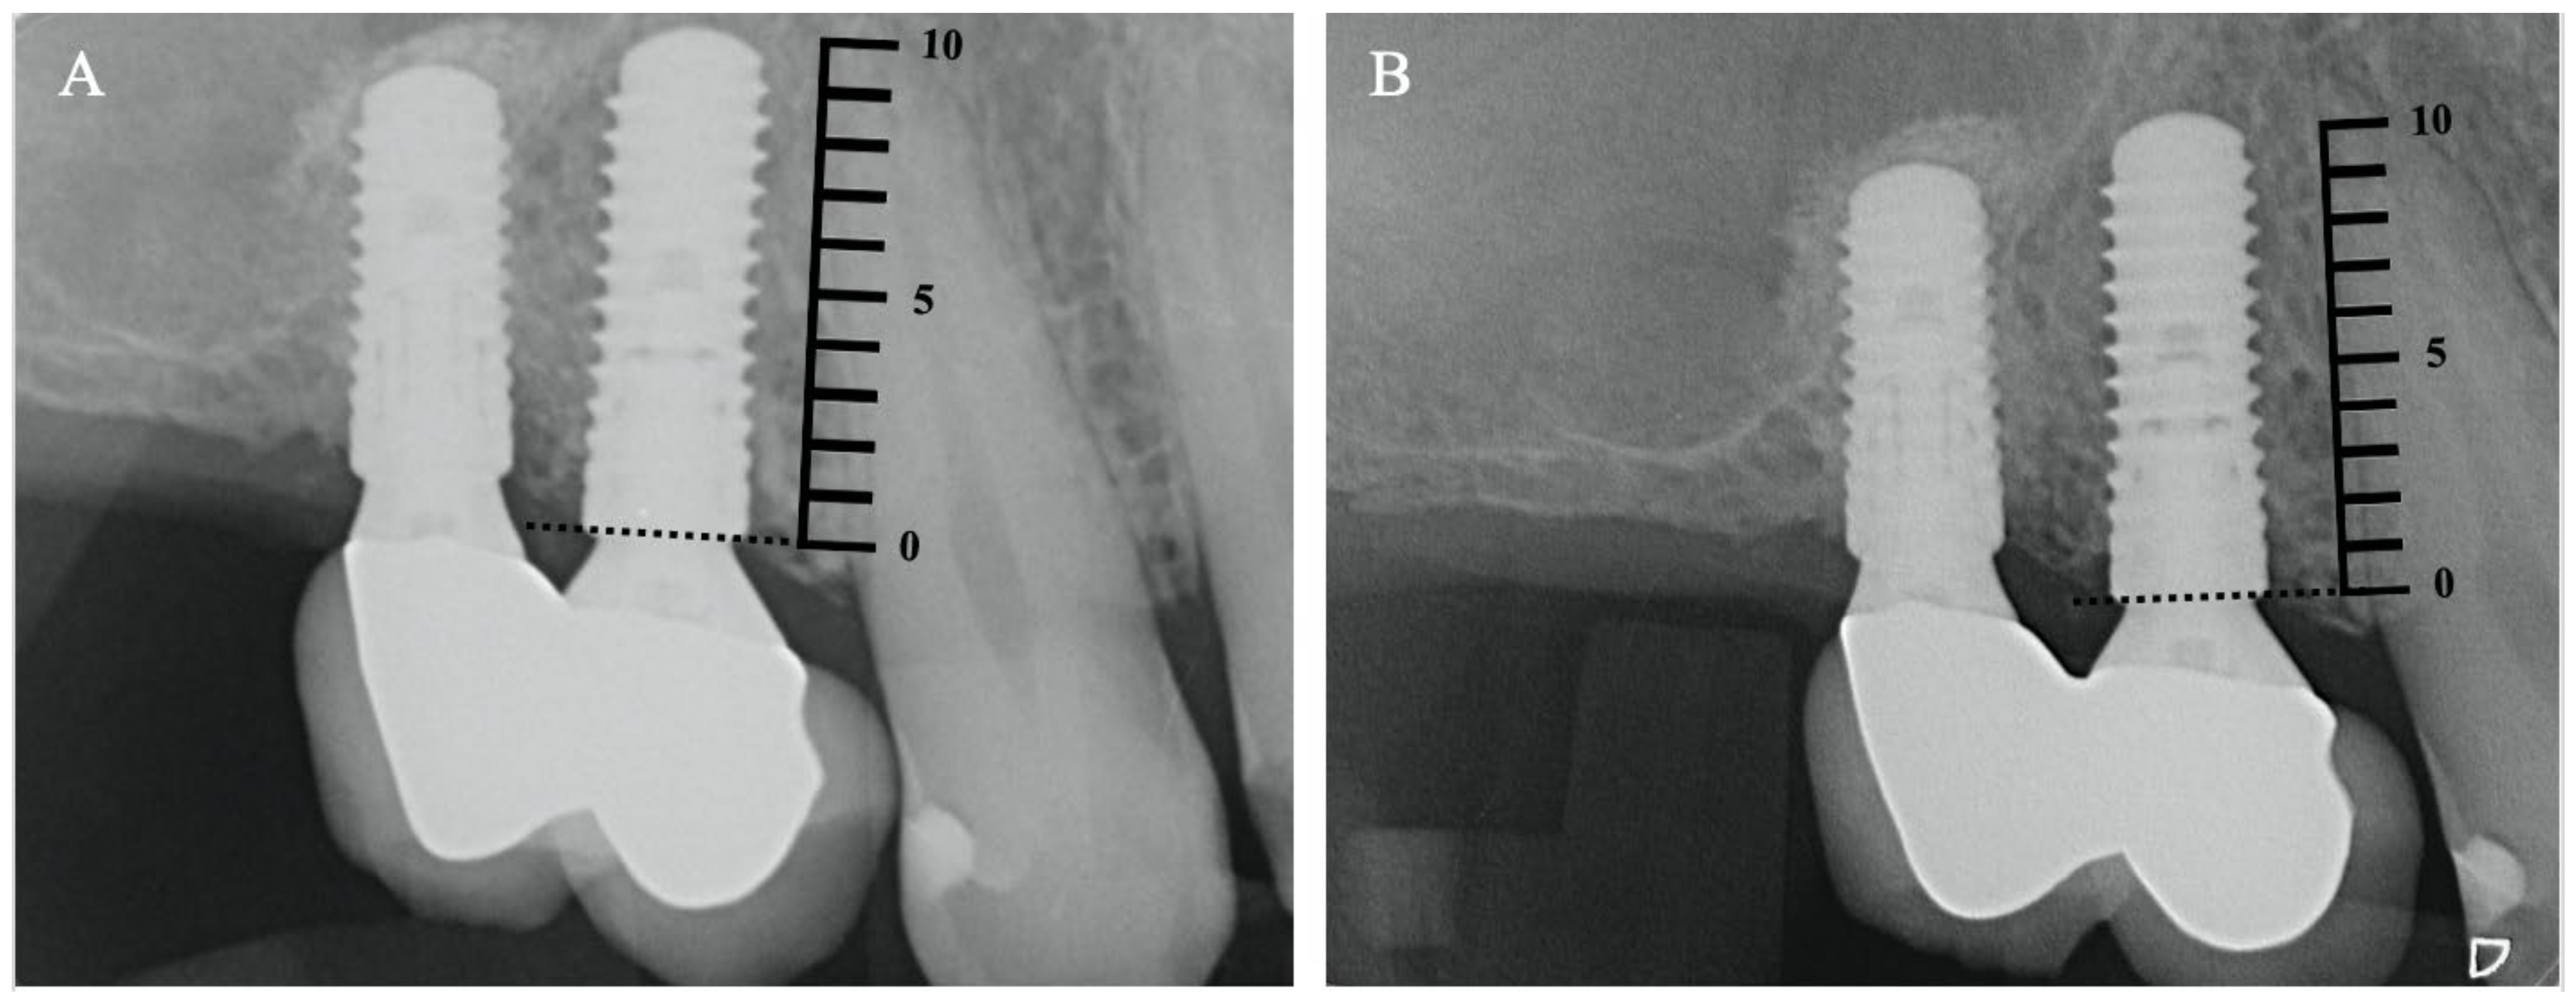

3.2. Clinical and Radiographic Analysis